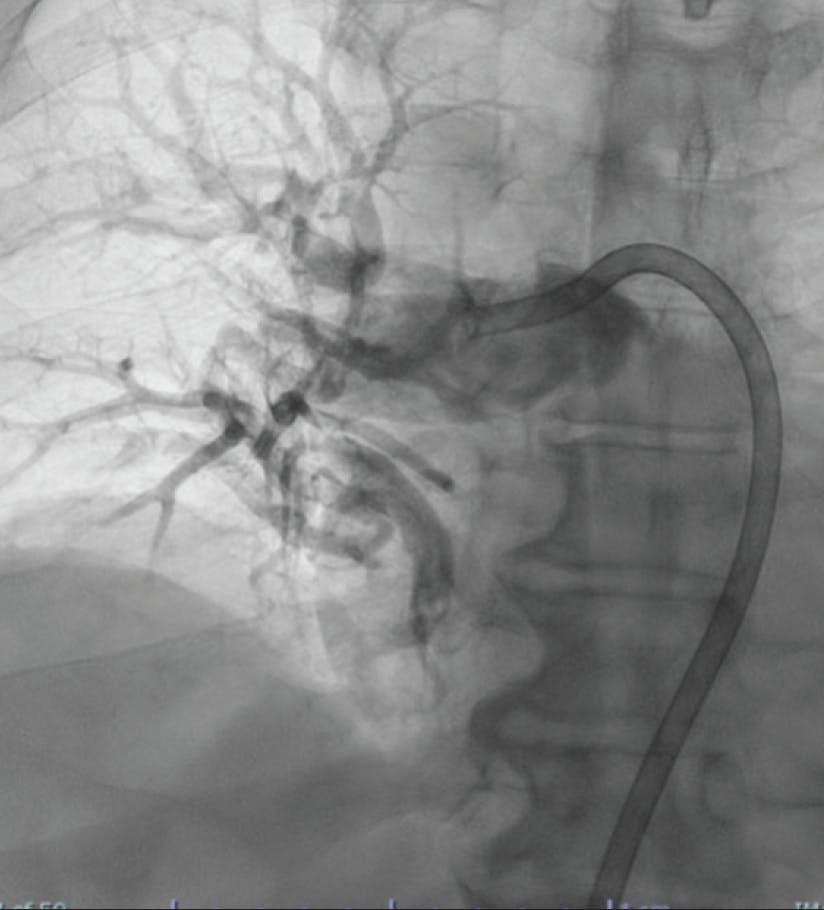

A woman in her early 70s with a medical history of hypertension, hyperlipidemia, peripheral artery disease, type 2 diabetes mellitus, and a recent diagnosis of stage IV pancreatic cancer presented to the emergency department with hour-long chest pain and dyspnea, as well as cramping in the right calf. She underwent the CT pulmonary embolism (PE) protocol, which showed significant clot burden with a saddle PE extending into the bilateral main pulmonary arteries (PAs) (Figure 1 and Figure 2). Her lactate level was 8.2 mmol/L. She was started on a heparin drip and had evidence of hypoxia that required 3 L of nasal cannula. Initial vitals recorded a blood pressure of 117/82 mm Hg, heart rate of 96 bpm, SpO2 of 87%, and respiratory rate of 31 breaths per minute. There was evidence of right heart strain with a right ventricular/left ventricular (RV/LV) ratio of 1.4 by CT, as well as a high PE Severity Index. Given the large clot burden, marginal hemodynamics, and hypoxia, we decided to move forward with CAVT with Lightning Flash 2.0.

Figure 2. Initial angiogram of the right lobe.

INTERVENTION

After achieving wire access, the Lightning Flash 2.0 was inserted. While in “Gallop Mode,” the saddle clot burden and subsequently the left and right main PAs were aspirated. Once the algorithm returned to “Sampling Mode,” aspiration was turned off and angiograms were obtained to assess the progress. After 5 minutes of aspiration, reperfusion of the main PAs and distal branches was achieved (Figure 3, Figure 4, and Figure 5), with improvement in the patient’s vital signs and no device-related complications.